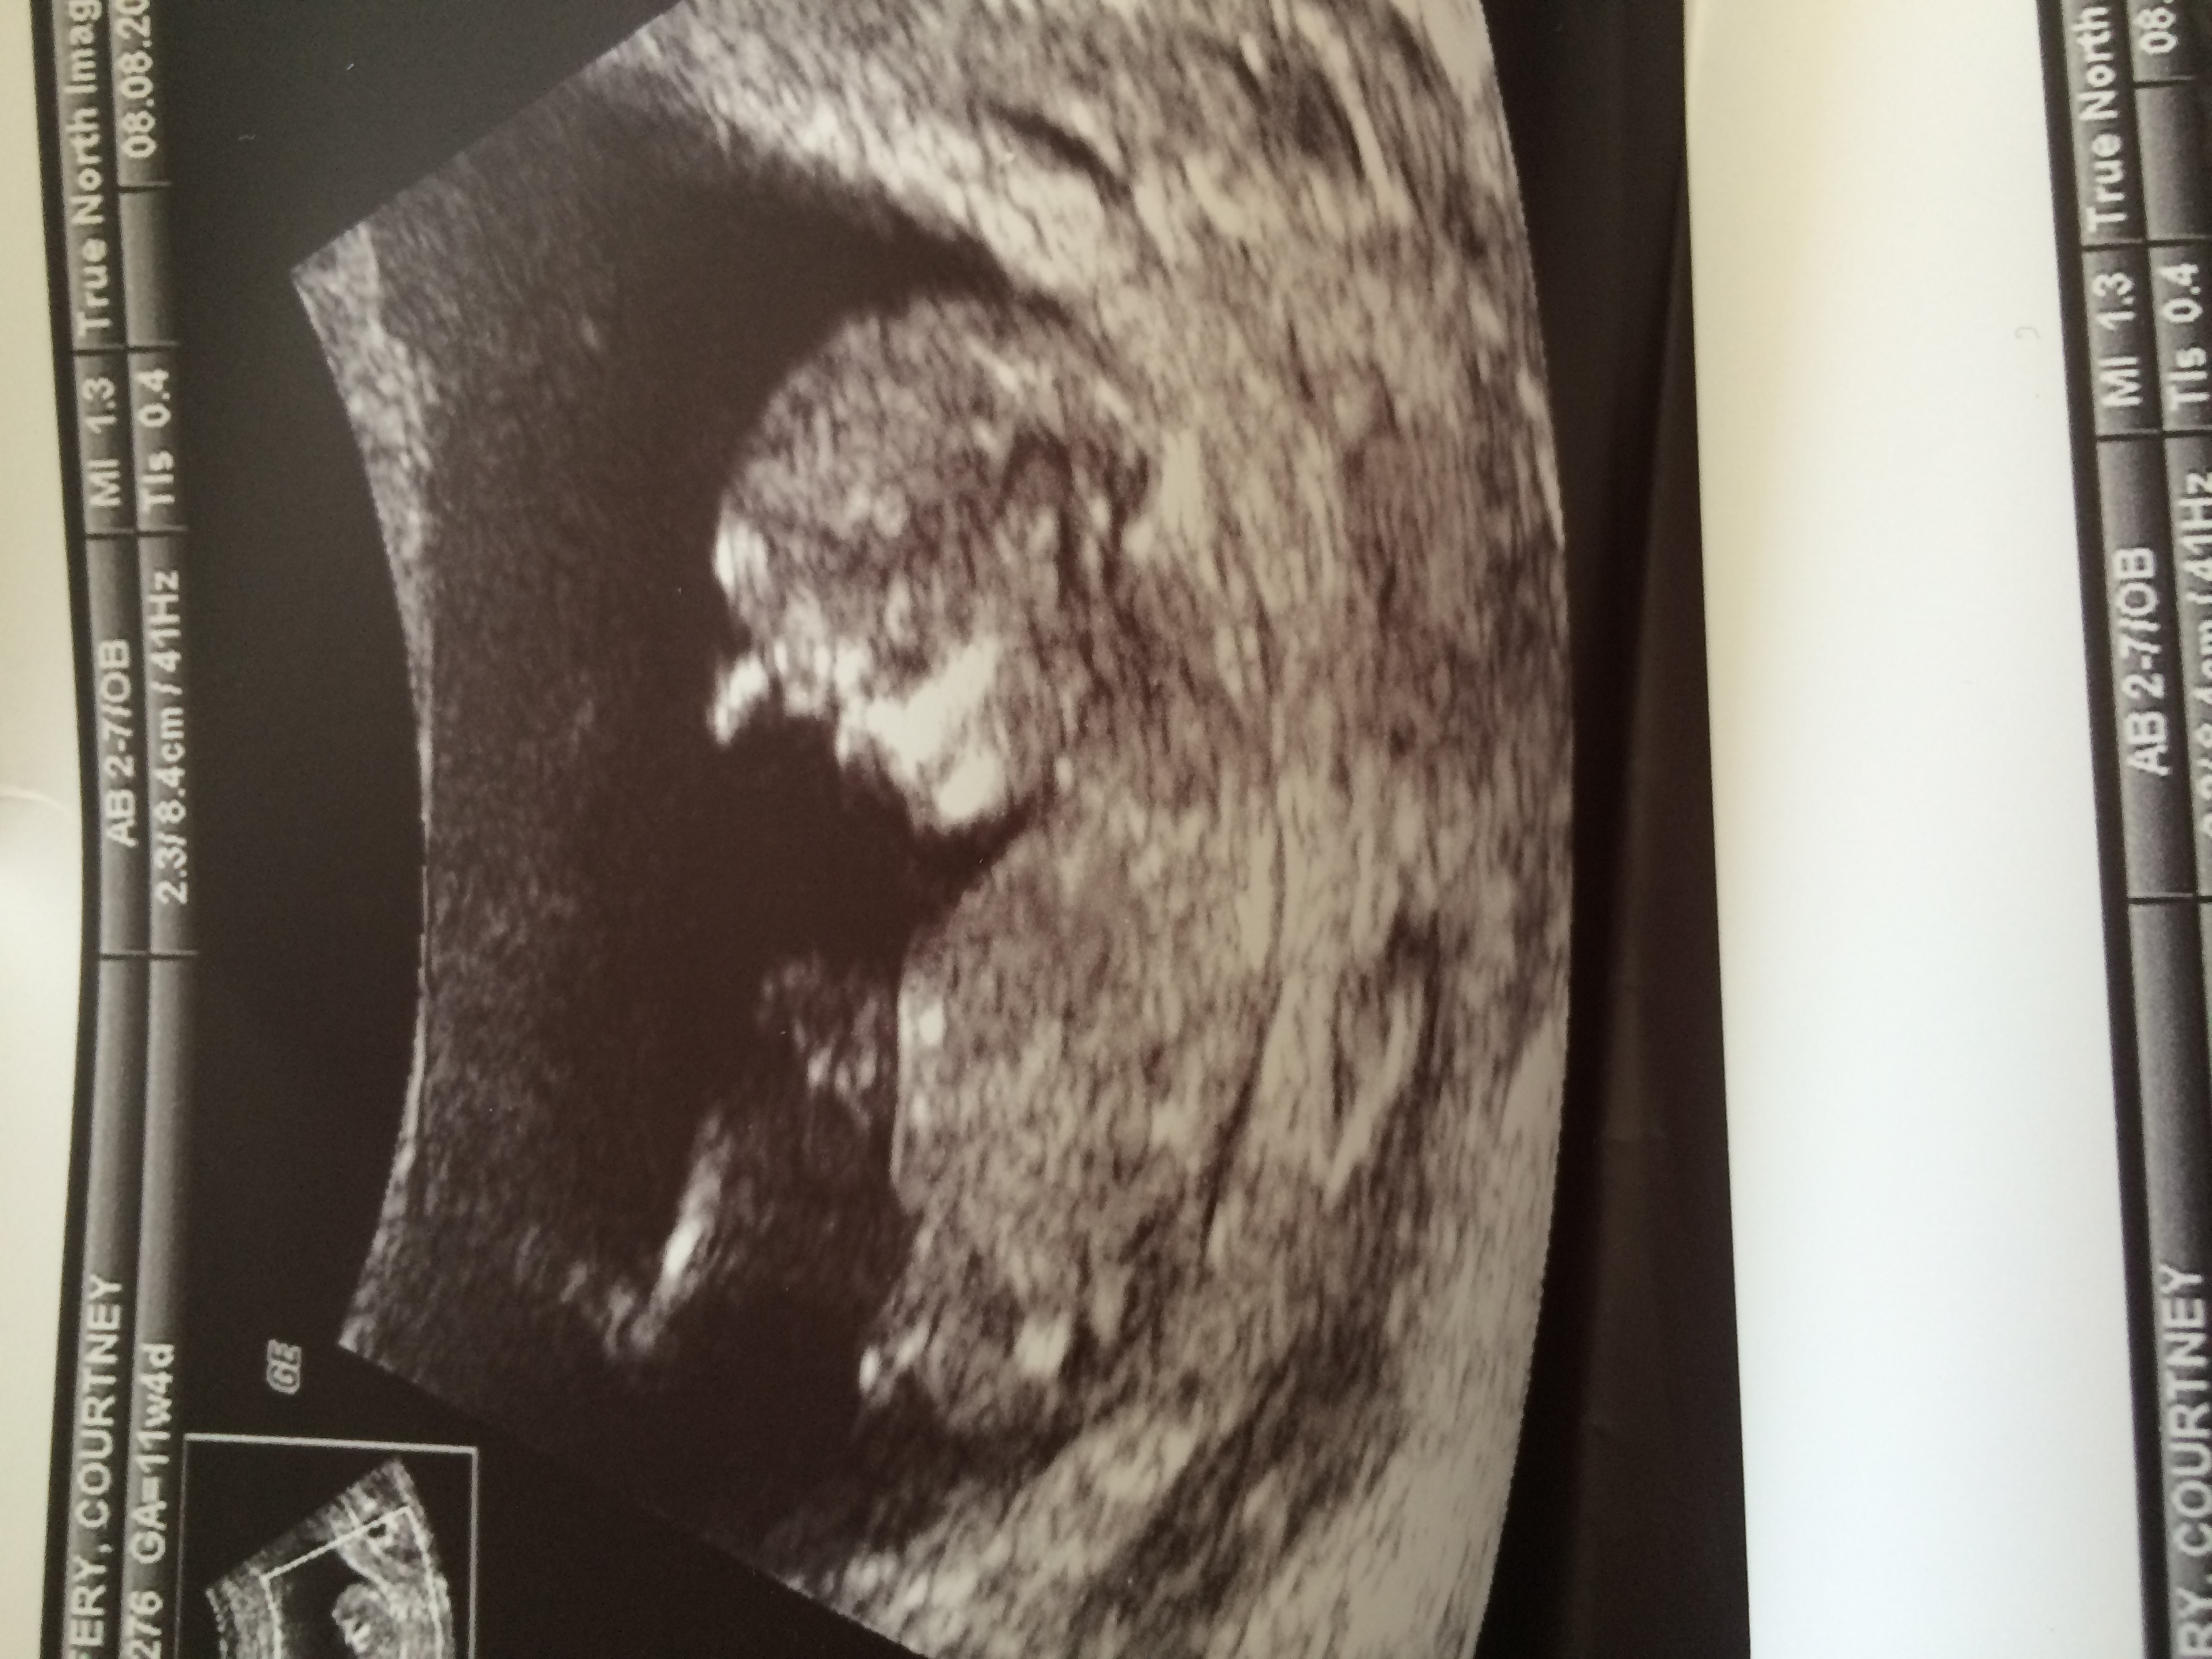

I'm new to the site and very interested in what everyone's opinion is on the gender of my baby! I got one shot of the nub but he/she wouldn't hold still to get another clear picture!

Please let me know your thoughts!

I have a prediction but wondering if anyone else thinks the same!